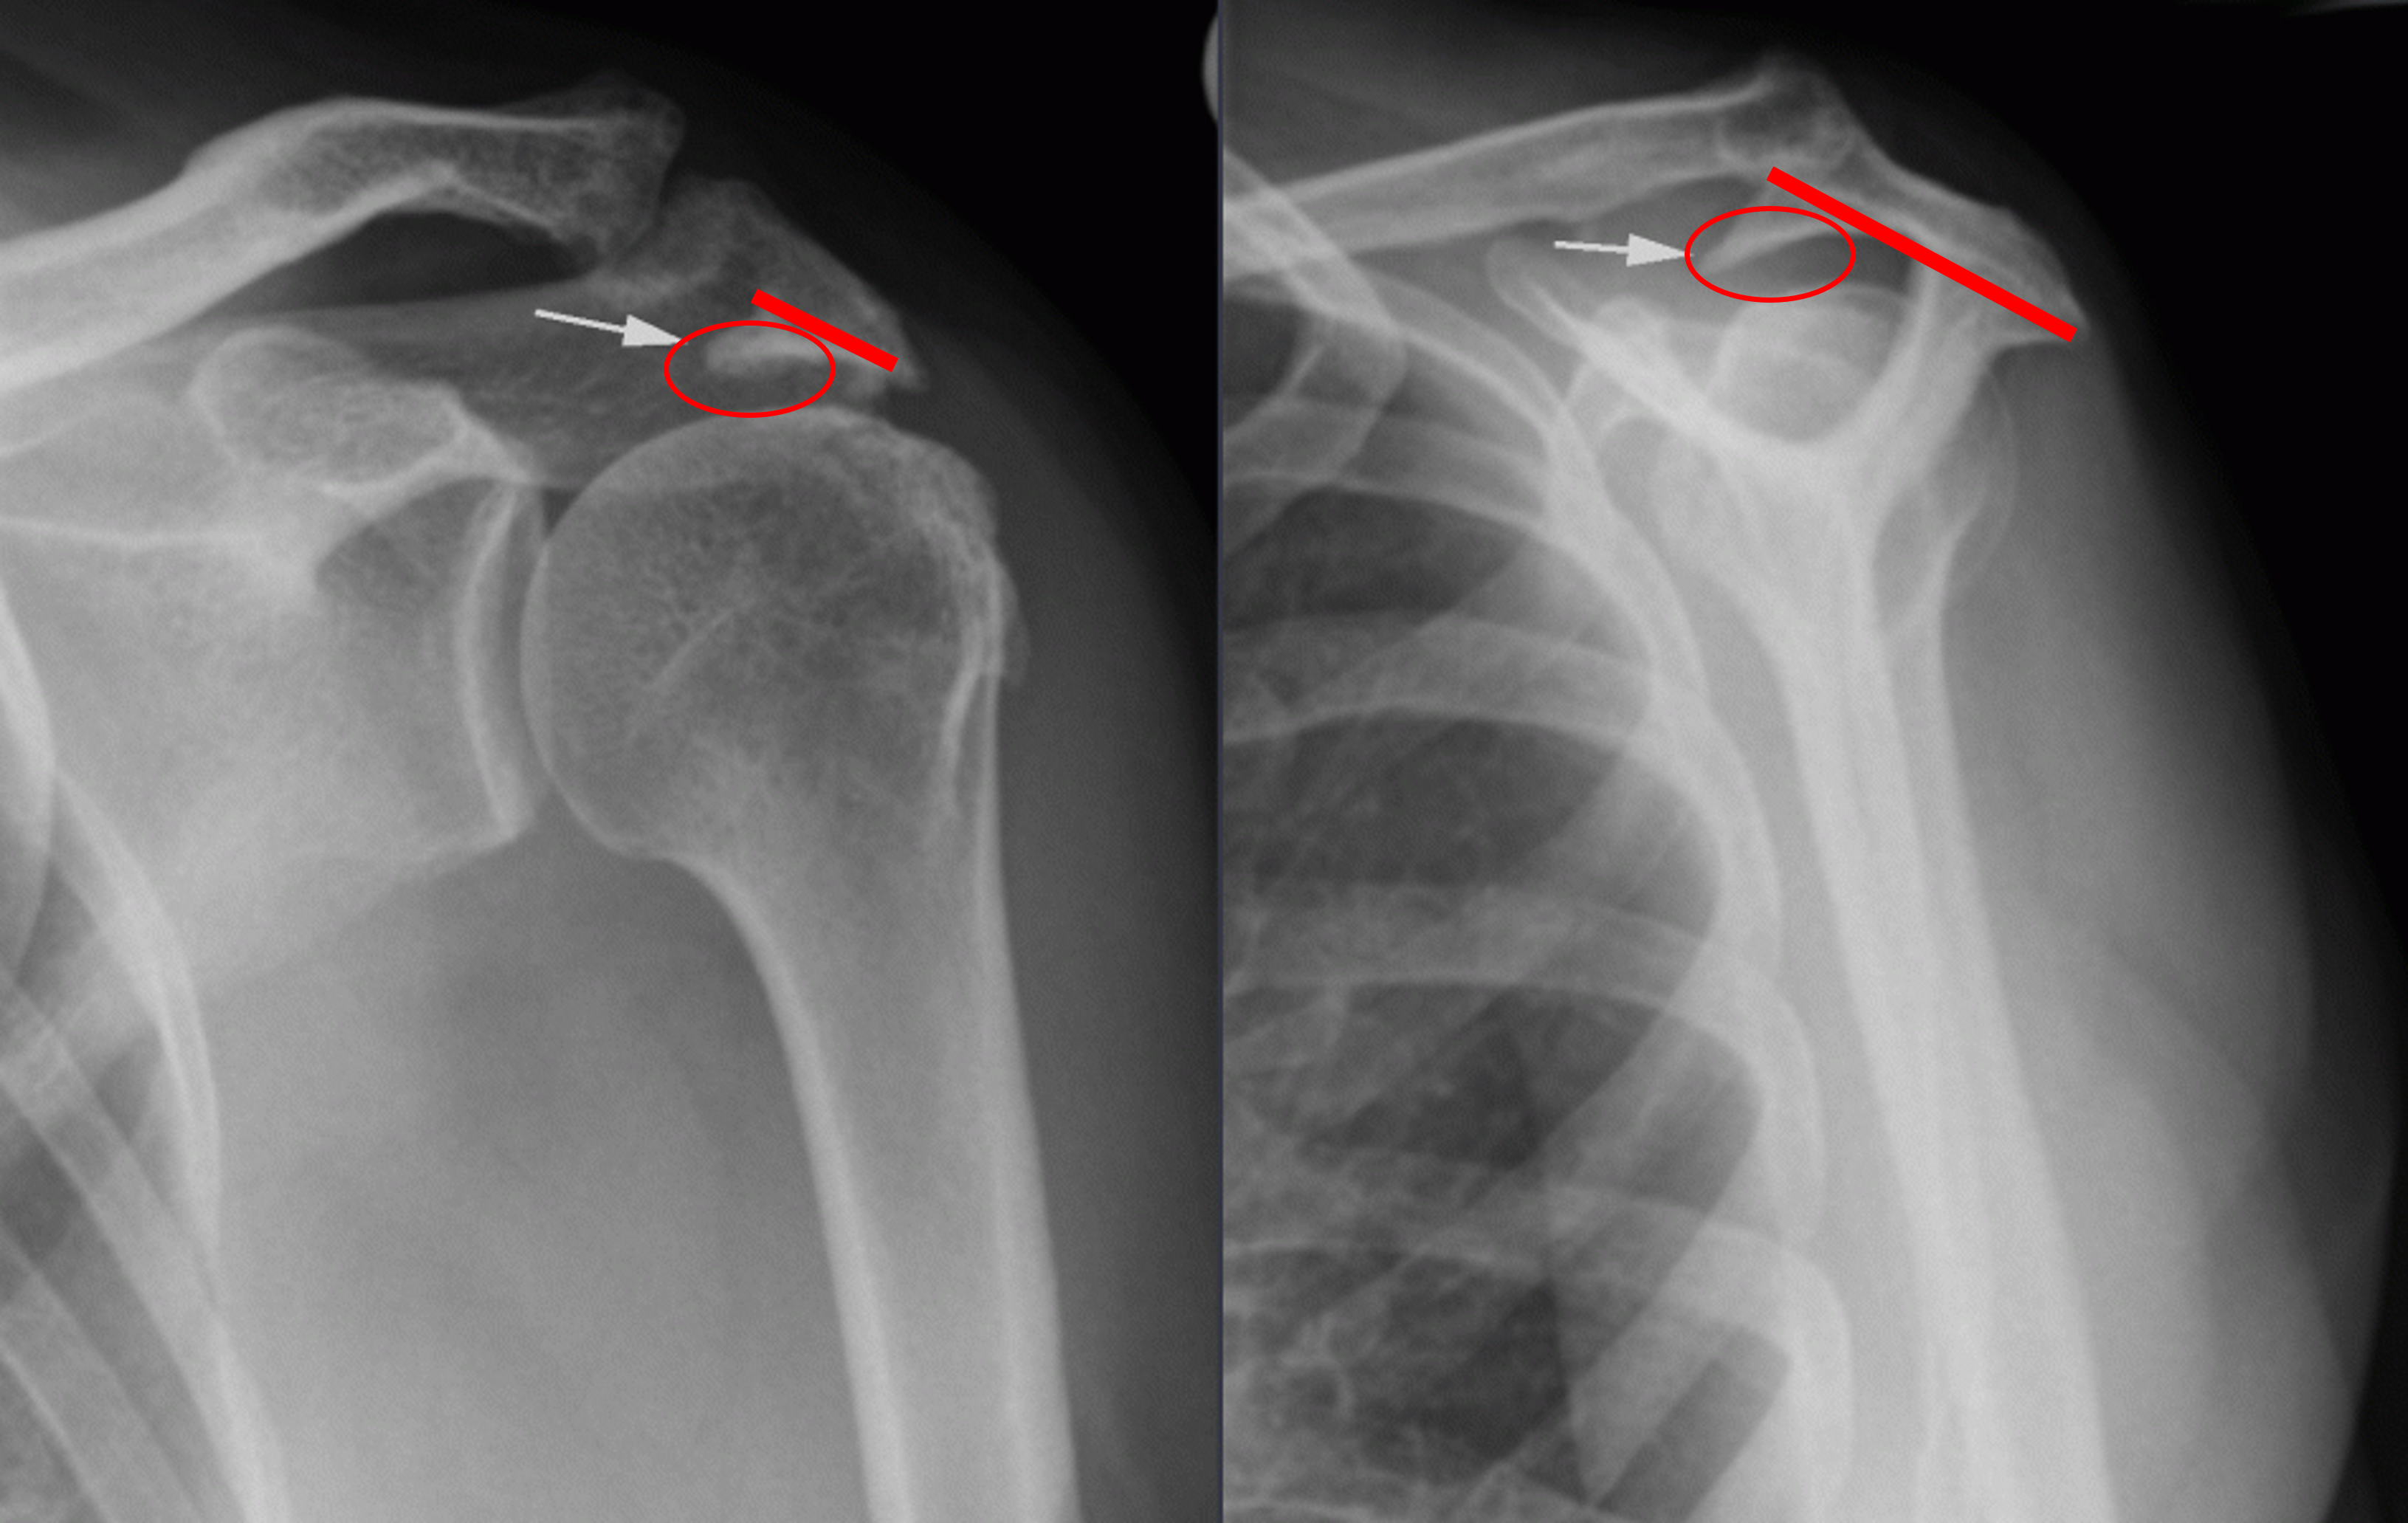

1. X-ray 검사 :

정형외과에 방문하시게되면 가장 많이 하시게 되시는 검사입니다. 가장 기본적이면서도 가장 먼저 감별해야할 위험한 진단을, 예를 들면 골절이나 골종양 등을 발견할 수 있게 해주는 값싸고도 고마운 검사입니다.

회전근개 파열에서 X-ray는 검사의 특성상, 직접적으로 인대를 시각적으로 보여줄 수 없기 때문에, 인대 그 자체에 대한 진단보다는, 인대의 파열을 유발할 수 있는 기저 병변이 있는지를 알아낼 수 있는 장치로써, 기본적으로 촬영하게 되는 검사입니다.

앞에서 말씀드린 회전근개 파열의 내인성 요인 중 하나인 석회가 있는지를 감별하게 해주며, 어깨를 많이 쓰는 직업을 가지신 환자분들의 경우, 극상건과 충돌하는 견봉에 퇴행성 변화중 하나인 '골극'이라는 뾰족하게 솟아오른 골조직을 확인할 수 있습니다. 이 골극이 심한 경우에는 이 골극 자체가 극상건에 손상을 가속하게 되므로, 회전근개 파열을 강력하게 의심할 수 있으며, 추후 수술 시에 단순하게 파열된 회전근개만을 봉합하는 것이 아니라, 추후 재 파열을 일으킬 수 있는 골극을 제거하기 위해서 계획을 짜는데 중요한 역할을 하게 됩니다.